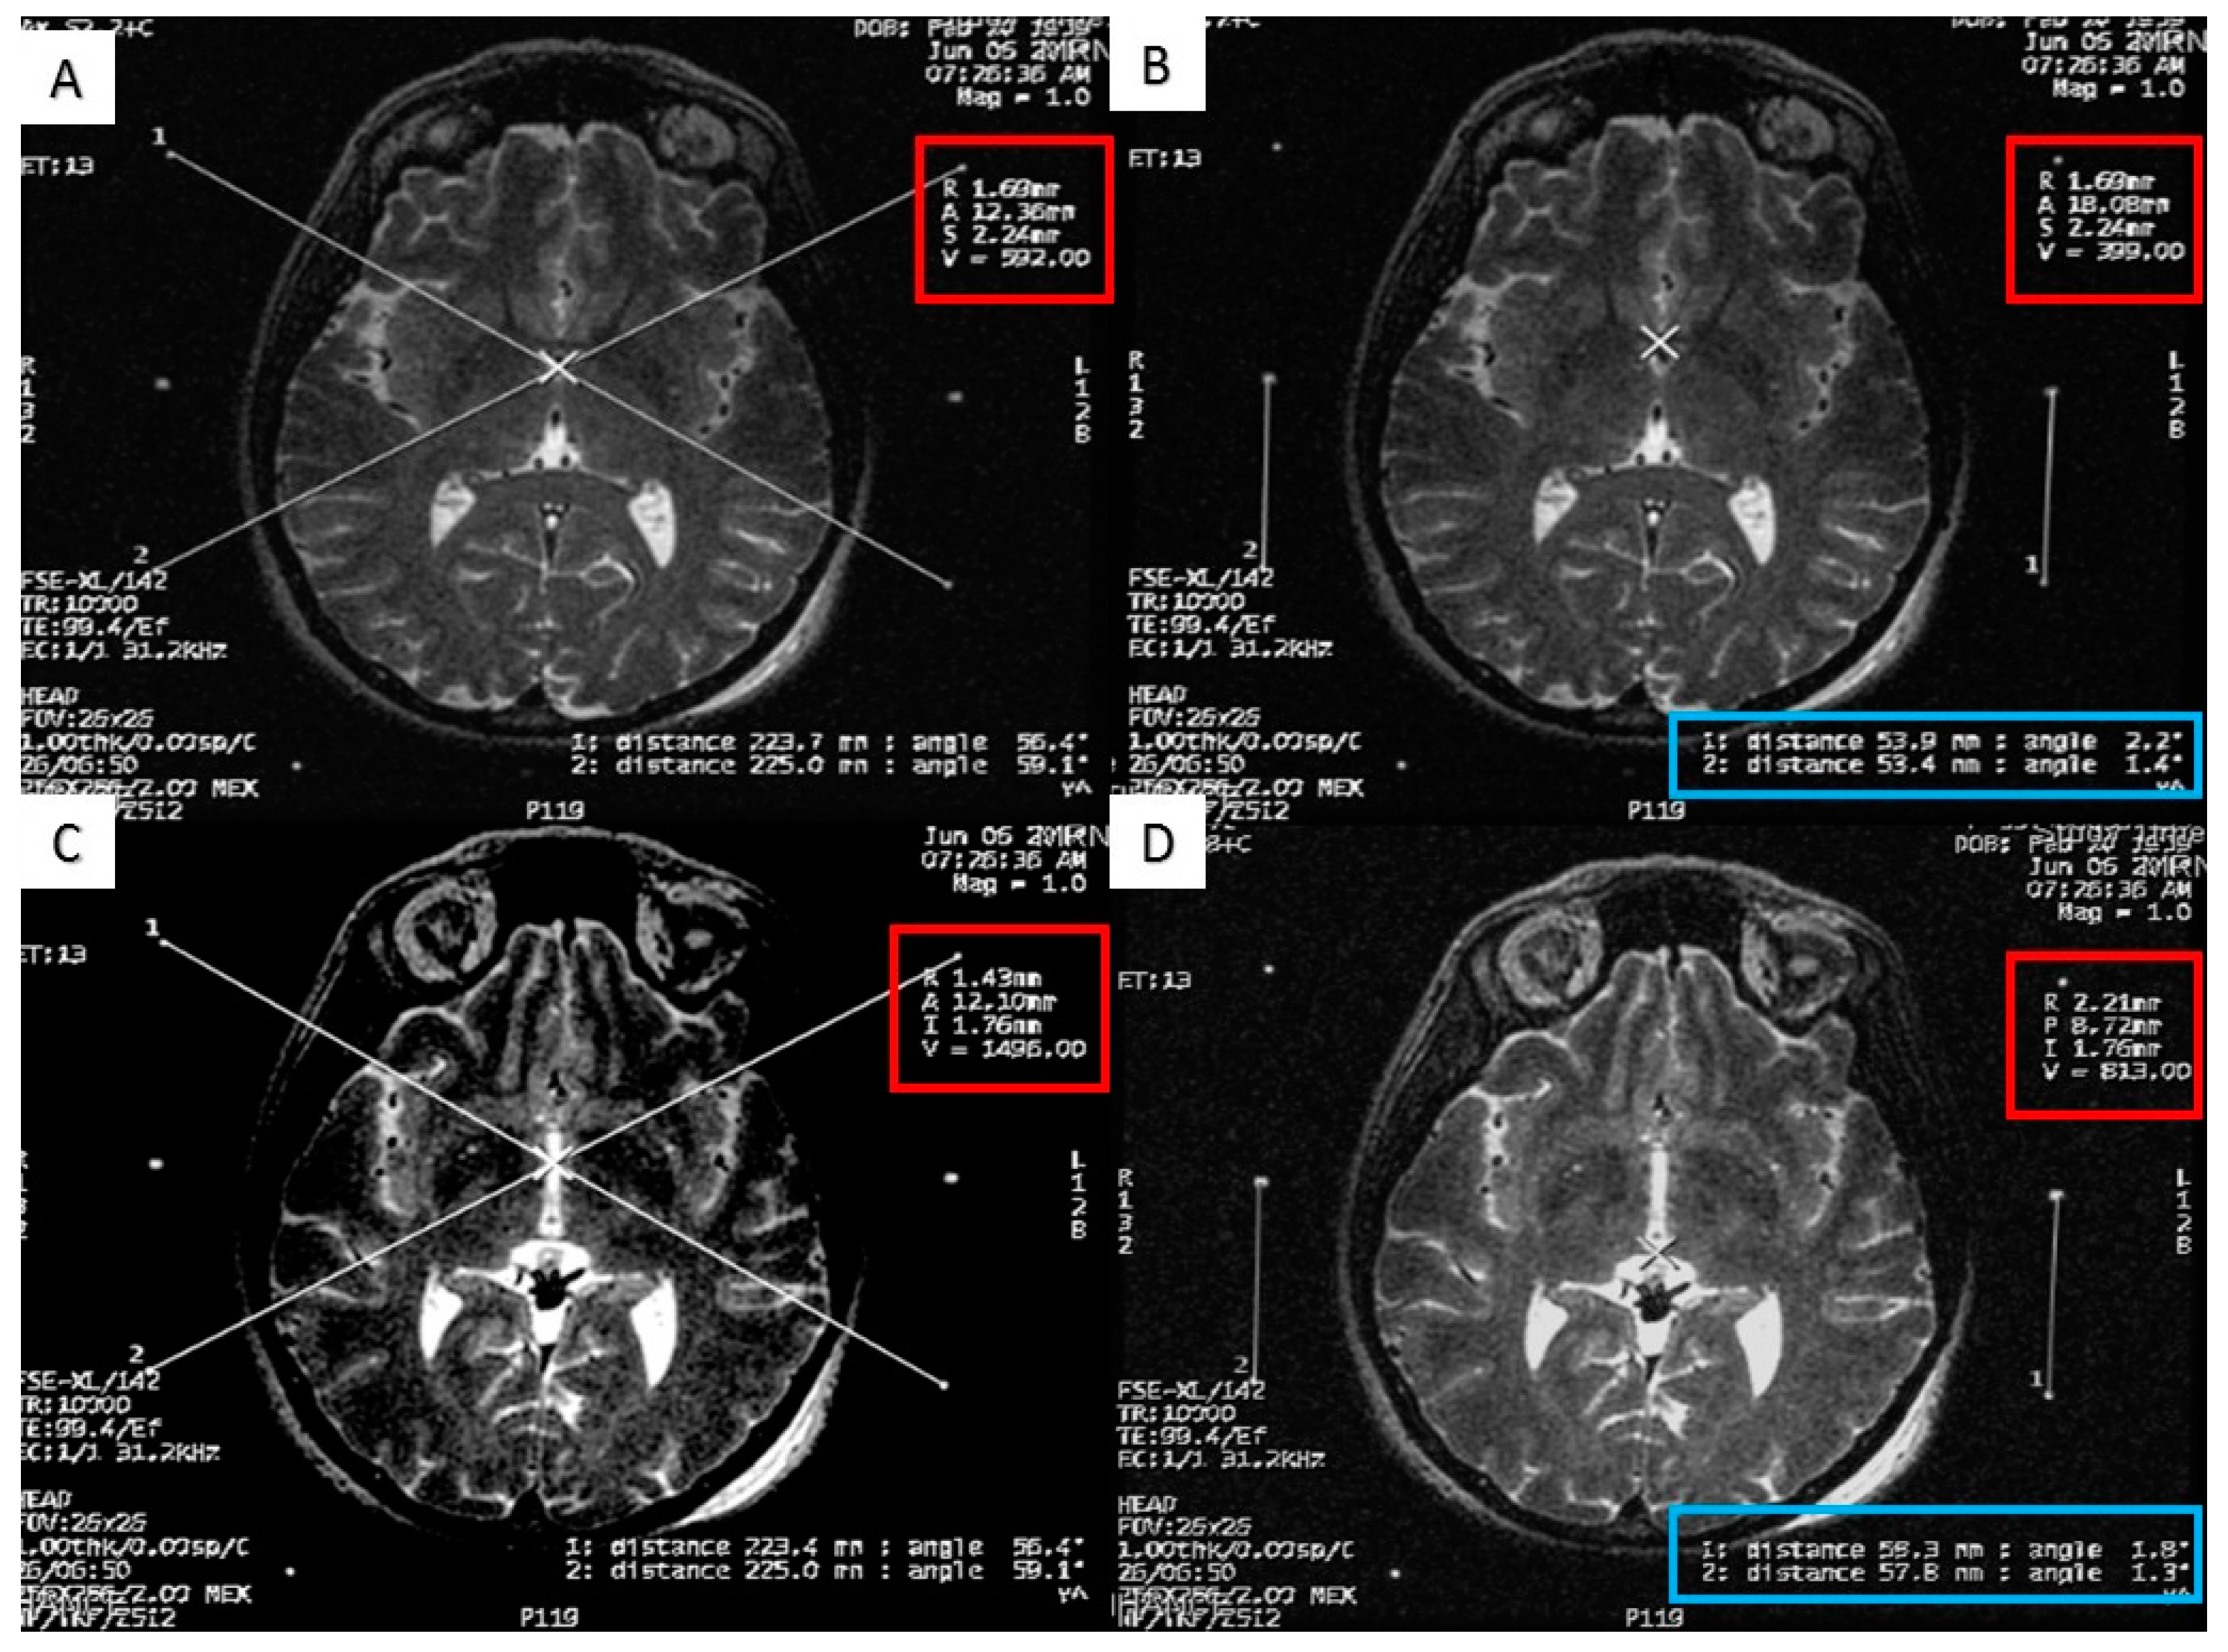

Figure 3.

Calculating the anterior commissure (AC) and posterior commissure (PC) coordinates using the magnetic resonance scanner console. (A) Two diagonal lines intersecting at the center of the frame at the AC level with the magnetic resonance imaging (MRI) coordinates of the center of the frame shown inside the red square; (B) a crosshair at the posterior margin of the AC, with the MRI coordinates of the AC shown inside the red square. Two lines are drawn between the middle and the lower fiducials on both sides of the frame and their lengths (in the blue rectangle) are used to calculate the Z coordinate of the AC; (C) two diagonal lines intersecting at the center of the frame at the PC level with the MRI coordinates of the center of the frame shown inside the red square; (D) a crosshair at the anterior margin of the PC, with the MRI coordinates of the PC shown inside the red square. Two lines are drawn between the middle and the lower fiducials on both sides of the frame and their lengths (in the blue rectangle) are used to calculate the Z coordinates of the PC.

At the end of the scan, we chose the axial T2 image (or two adjacent images) in which the anterior commissure (AC) and the posterior commissure (PC) are identified (Figure 2). Then, we measured the distance between the middle and lower fiducials on both sides of the frame, and a maximum of 2 mm difference was allowed. The X and Y MR coordinate of the center of the frame was obtained at the point of meeting of two diagonal lines drawn on the MR console between the opposing anterior and posterior fiducials. After that, the X and Y MR coordinates of both the AC, the PC, and the center of the frame (Figure 3) were obtained from the MR console, and entered into a simple Excel worksheet (Microsoft, Redmond, WA, USA) designed by the senior author.

Afterwards, the frame coordinates of the AC, PC, the mid-commissural point (MCP), and the intercommissural distance (should be from 21 to 28 mm) were calculated with the help of this Excel worksheet by using the following formulas: